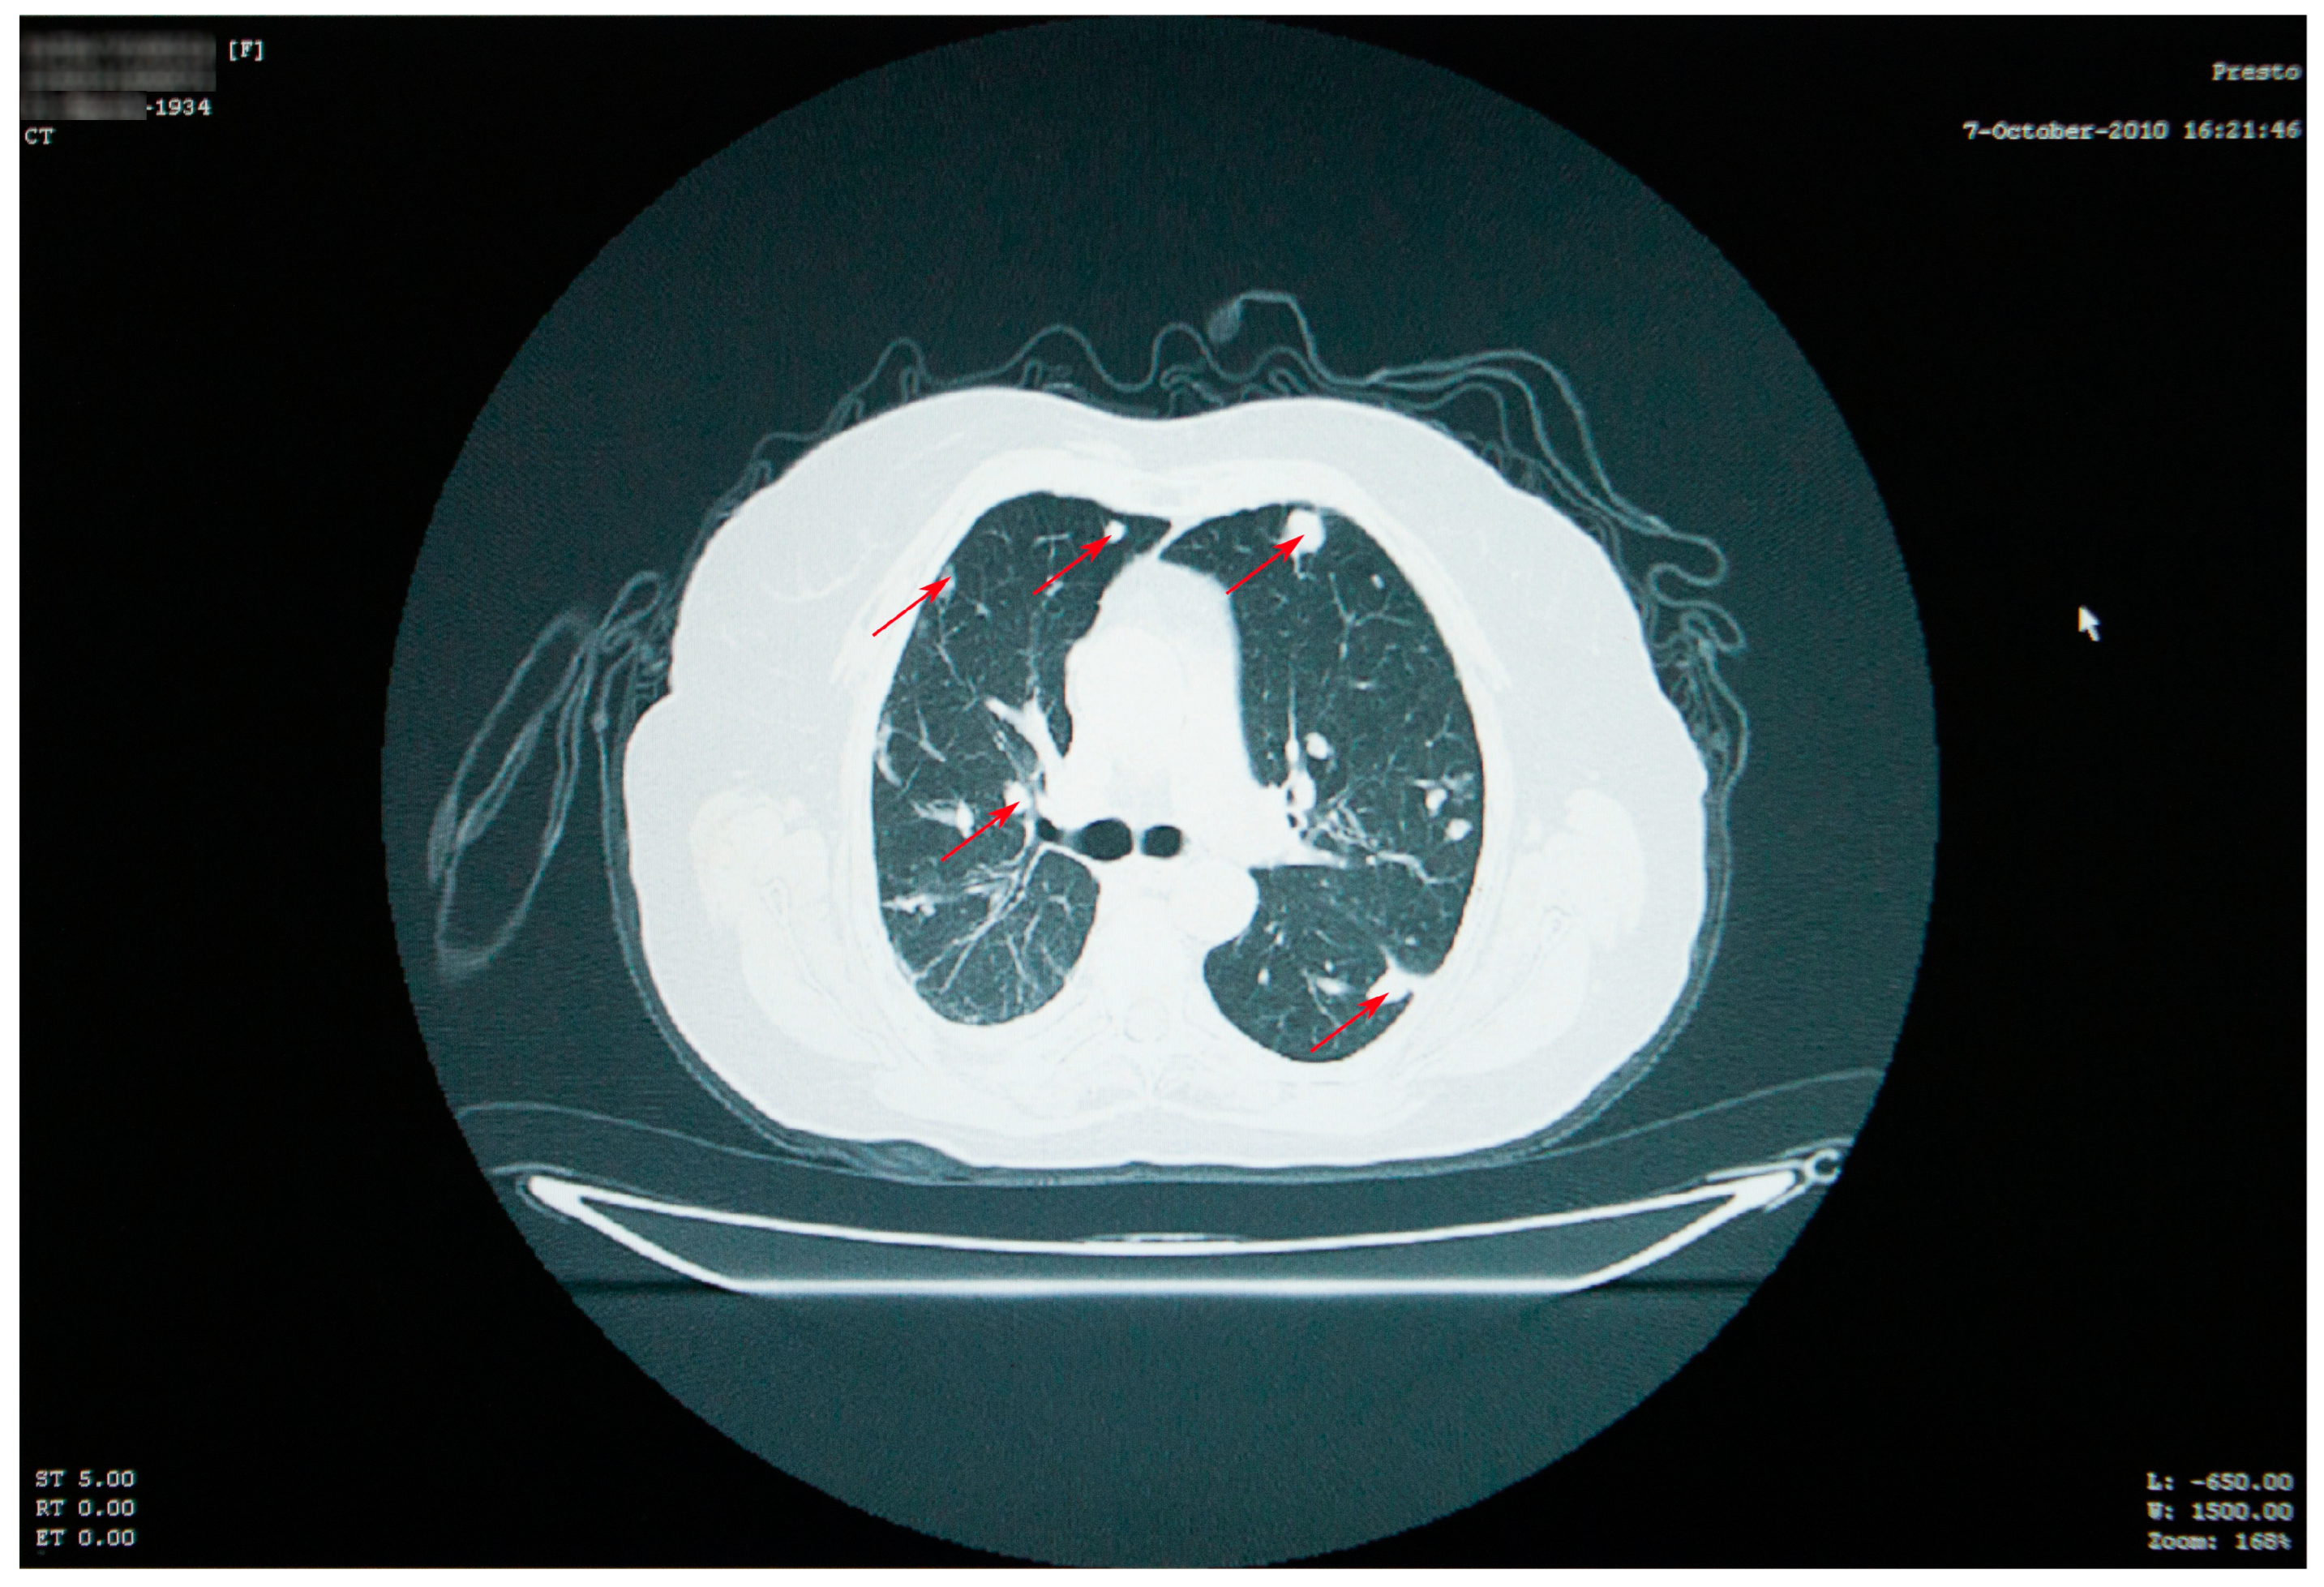

Thoracic and abdominal CT scans were performed, which revealed numerous thoracic masses, located in both the lungs and the pleura, round or oval in shape, centimetric or millimetric in size, with different consistencies, some liquid with calcifications, some condensed, sometimes clustering, as well as bilateral pachypleuritis, more pronounced on the right side (Figure 2).

Figure 2. Thoracic CT scan showing numerous thoracic masses (red arrows), located bilaterally, with different consistencies, and bilateral pachypleuritis.